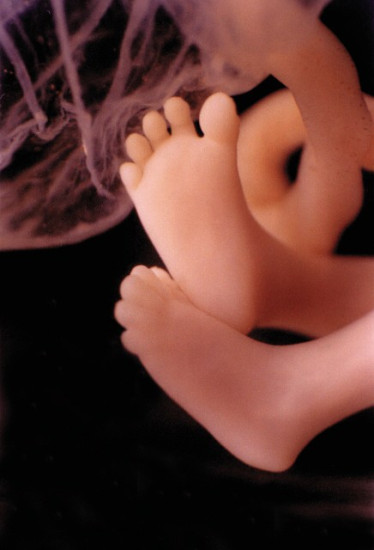

W 11. tygodniu życia wszystkie narządy dziecka są już ukształtowane. Ich doskonalenie jednak trochę jeszcze potrwa. Maleństwo ćwiczy nowe ruchy i staje się coraz sprawniejsze.

Dziecko ma już 6,5 cm długości, czyli tyle, ile cytryna. Waży 9,5 g. Skacze w Twoim brzuchu jak astronauta, choć jeszcze wcale tego nie czujesz.